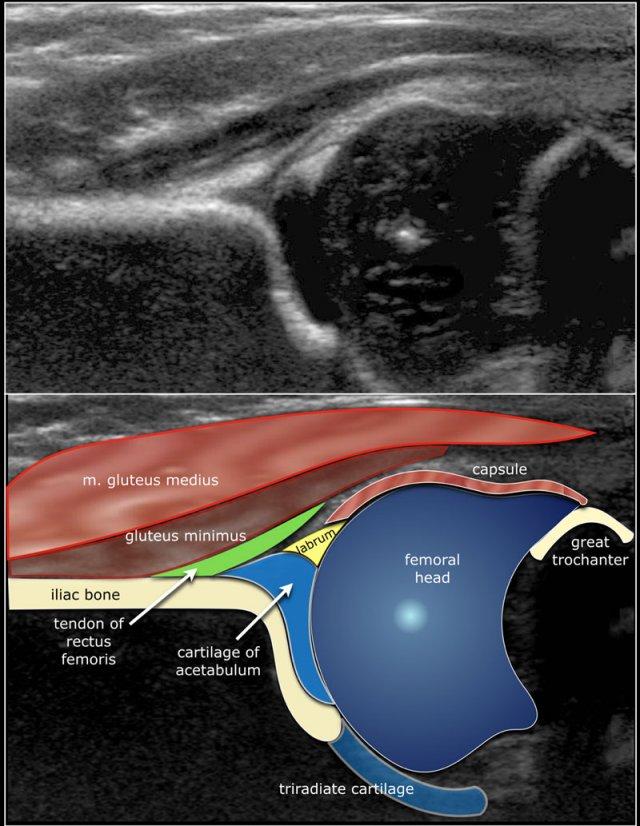

Do đó, phân loại loạn sản khớp háng theo Graf chủ yếu dựa trên hình thái xương chậu, trong đó chúng ta xem xét hình dạng của ổ cối, bờ ổ cối xương và sụn, sụn viền và vị trí của chỏm xương đùi.

Vì siêu âm có ưu điểm là cũng hiển thị được các cấu trúc sụn, chúng ta có thể quan sát mức độ che phủ của chỏm xương đùi bởi sụn ổ cối và sụn viền.

Vì trẻ sơ sinh đang nằm nghiêng nên cấu trúc giải phẫu được hiển thị theo chiều ngang thay vì chiều dọc (hình)

Và đây là cách hình ảnh siêu âm được hiển thị trên màn hình của máy siêu âm

In this video the ultrasound anatomy is shown.

Here the anatomy in the coronal plane.